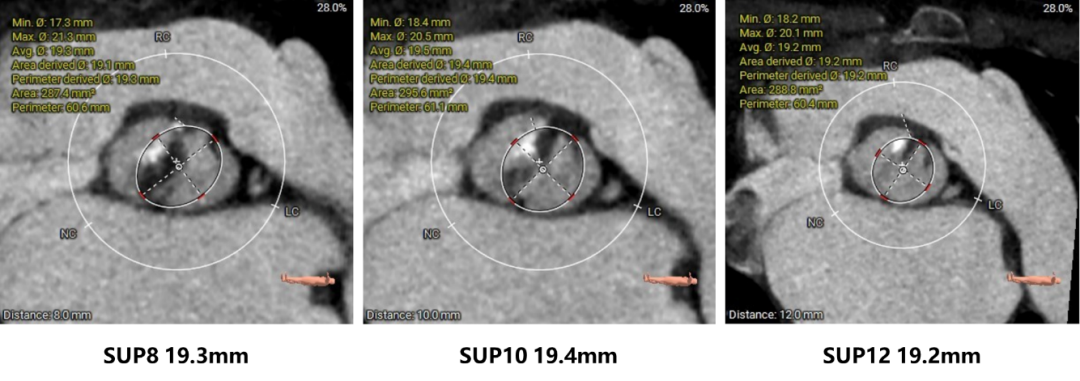

主动脉根部评估:

瓣环上结构测量: